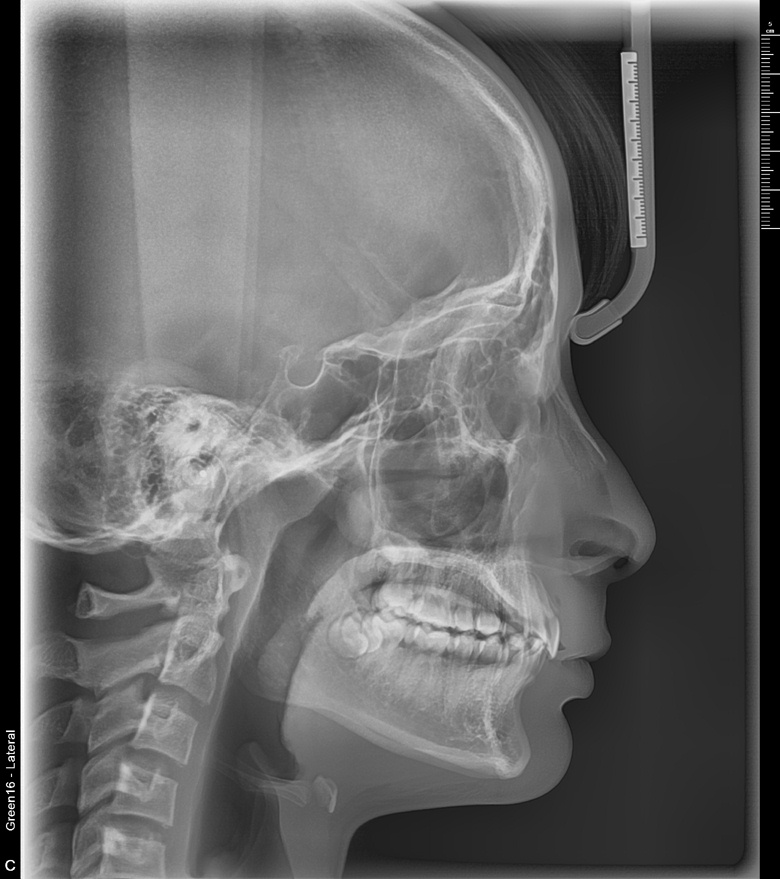

치료 후 사진입니다.